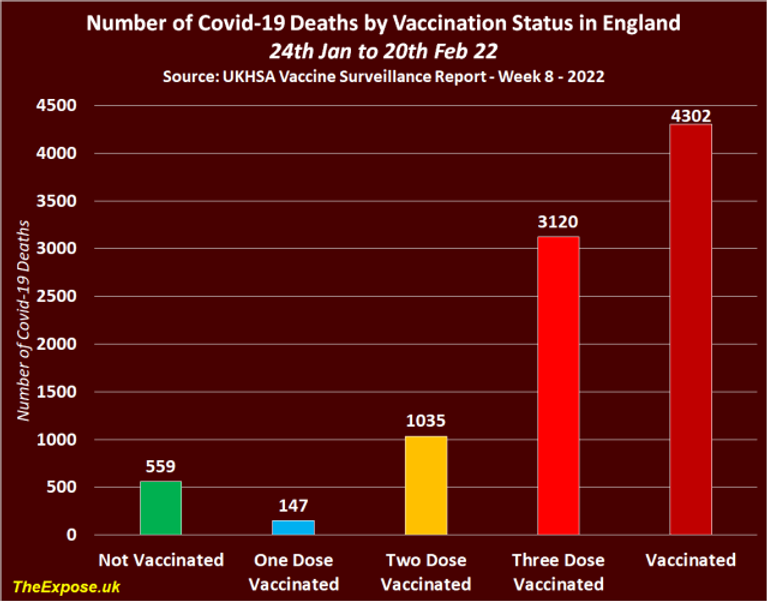

In all, there were 4,861 Covid-19 deaths between 24th of January and the 20th of February, 2022, and the triple vaccinated population accounted for 3,120 deaths. Whilst the nonvaccinated population accounted for just 559 deaths.

Overall, the vaccinated population accounted for 89% of all Covid-19 deaths during these four weeks, with 4,302 recorded deaths. This means the vaccinated population now account for 9 in every 10 deaths, and the triple vaccinated population account for 4 in every 5 deaths.

Deaths among the nonvaccinated have fallen from 889 between 22nd Nov and 19th Dec 21, to 559 between 24th Jan and 20th Feb 22. This represents a 37% decrease in overall deaths.

But deaths of the vaccinated population have increased from 2,913 between 22nd of November and 19th of December, 2021, to 4,302 between 24th of January and the 20th of February, 2022. This represents a 48% increase in overall deaths.

These are NOT the kind of figures you would expect to see if the Covid-19 injections really were up to 95% effective at preventing hospitalization and death, are they?